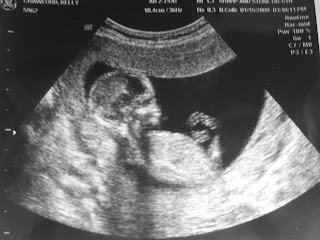

My first appointment with the doctor went really well, except that I am not as far along as I thought I was! I am only 14 weeks as opposed to 17 weeks. (Which relieved my fears about not having felt the baby move yet.)

But the baby looked healthy and we are praising the Lord for that! Also, my doctor assured me that the thyroid was not low enough to effect him/her, so that was a great relief.

Only 14 weeks and fully formed. Beautiful! What a blessing!

Wow, Kelly, I’m just amazed at the Dr.’s emotional reaction. That is such a blessing! It’s very rare to have that kind of conversation with a OB doc, I’m sure. What a strong testimony your family is in this world! I thank God for you!And what a sweet first portrait of your little one. Congratulations to your entire family!